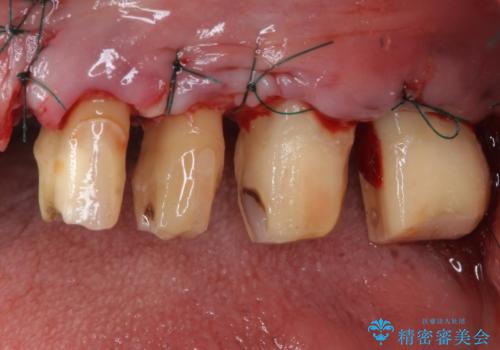

- 歯を磨く度に奥歯から出血するとのことで来院された患者様です。

歯周ポケット検査を行ったところ、6-8mmの歯周ポケットが散見され(正常では3mm以下)、歯周病治療が必要と判断されました。

仮歯に置き替え、歯周外科処置(APF、歯肉弁根尖側移動術)による歯周ポケット除去を行った後に、オールセラミッククラウンにて補綴することとしました。

歯周外科処置により歯周ポケットを除去することができ、クラウン装着後はブラッシング時の出血や歯肉の腫れが気にならなくなりました。